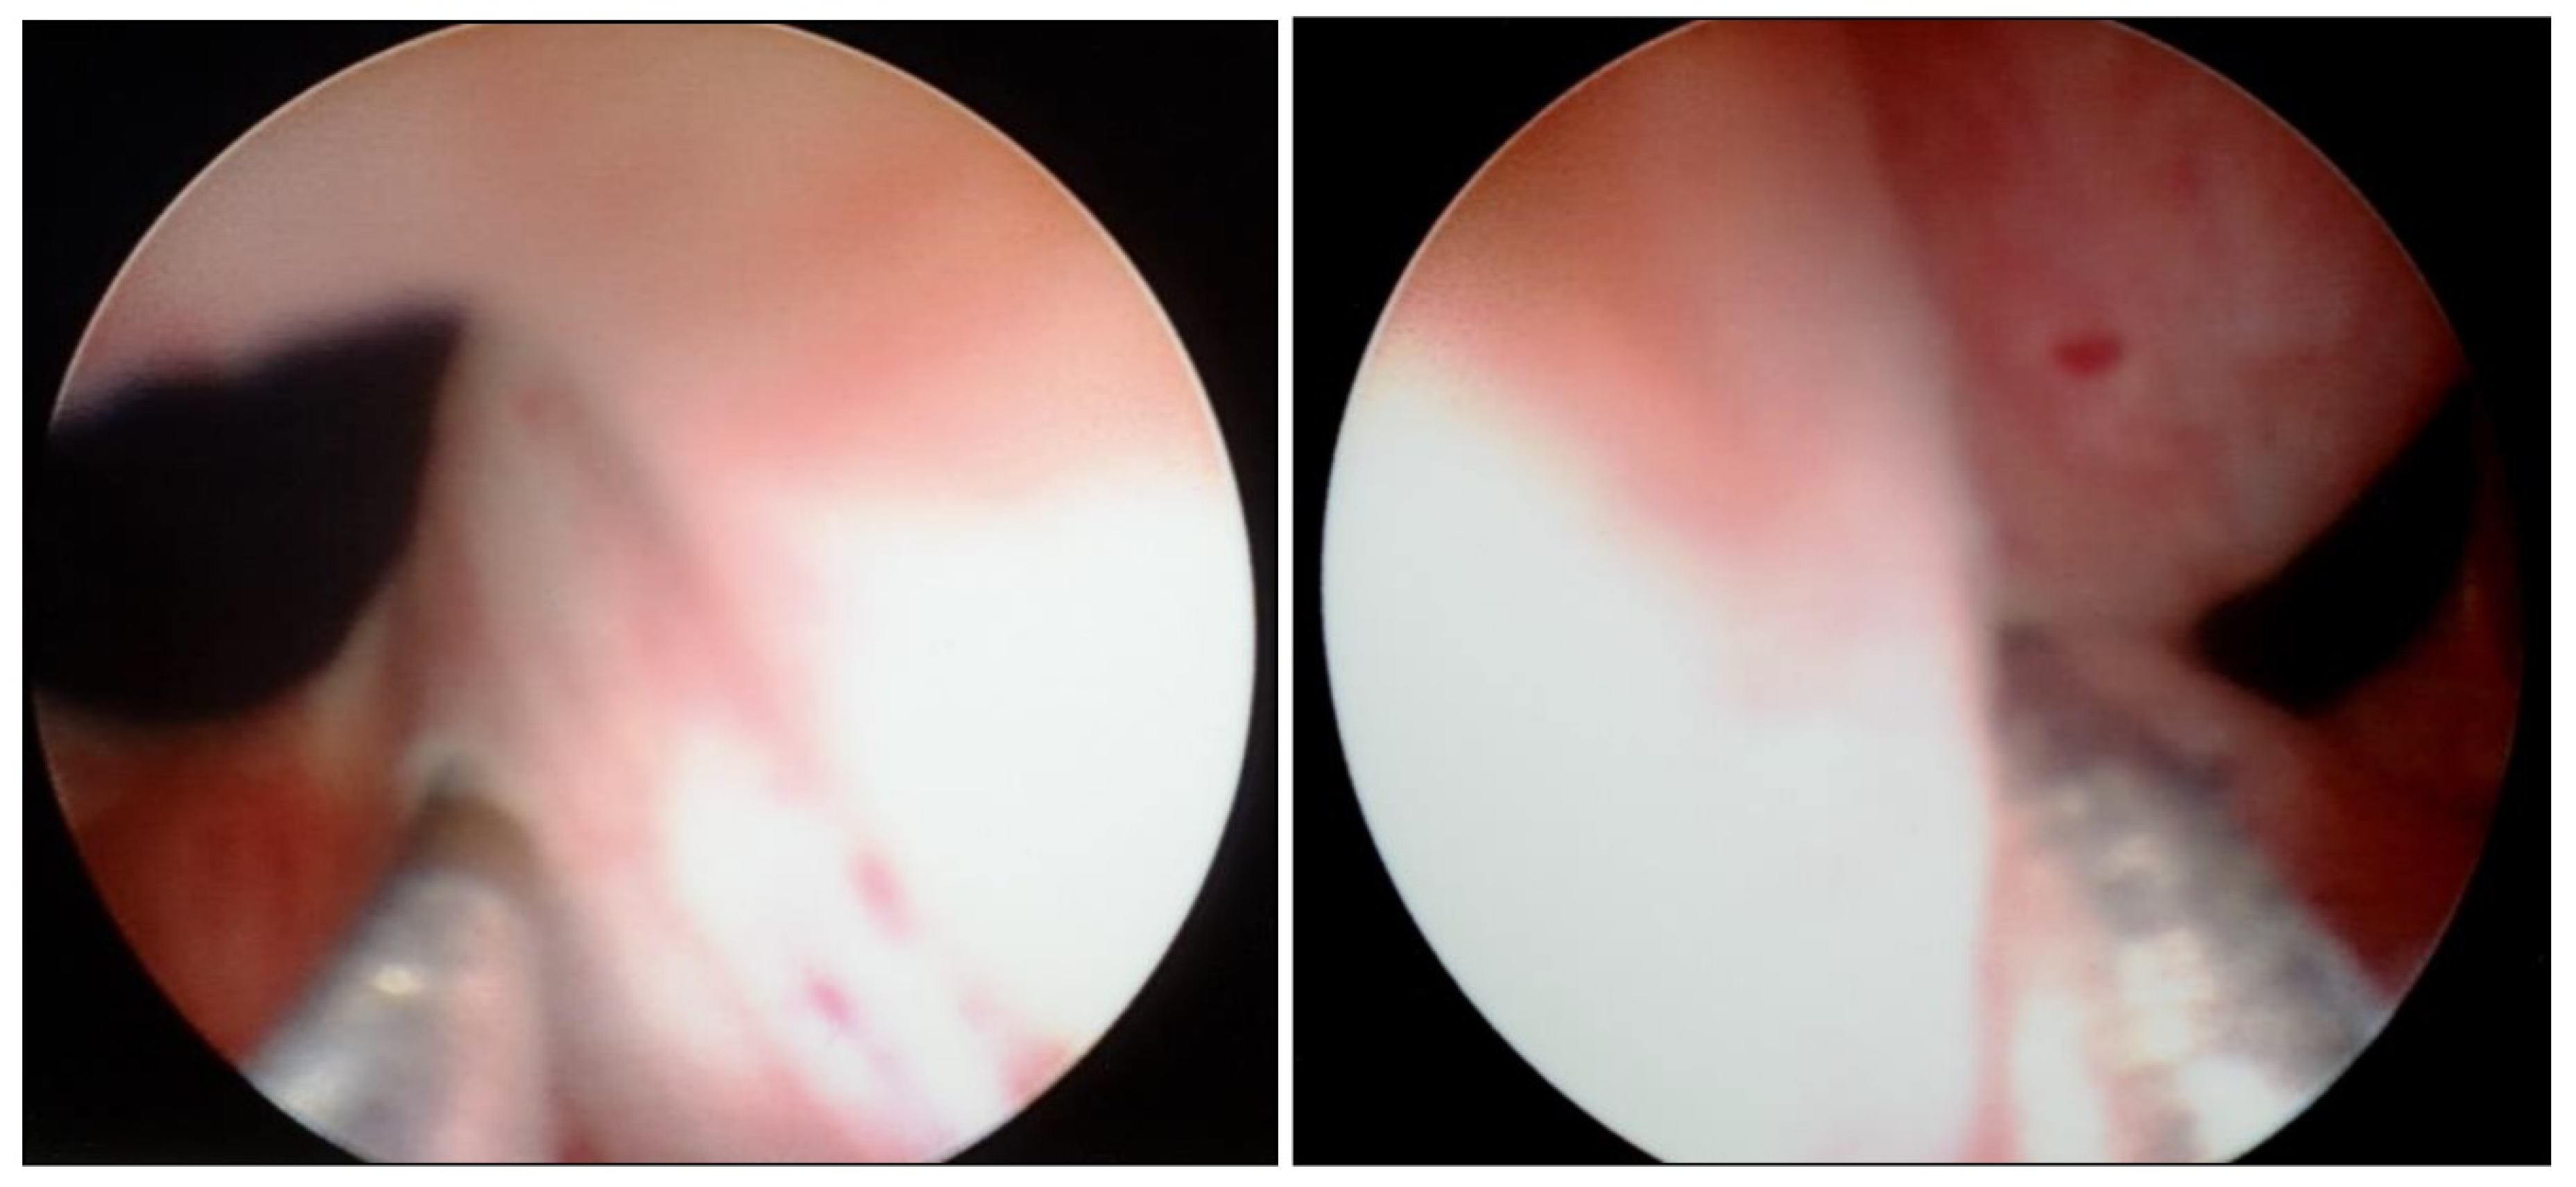

Transurethral cystoscopy displayed a wide open bladder neck at the beginning of the procedure (Figure 5). Under guidance by antegrade suprapubic endoscopy, transurethral retrograde bladder neck injection was performed at the 3 o’clock and 9 o’clock positions (Figure 6). Subsequently, bladder neck injection at the 6 o’clock and 12 o’clock positions was performed through antegrade percutaneous suprapubic endoscopy. Direct antegrade and retrograde visualization confirmed effectiveness of the luminal occlusion (Figure 7). As a (positive) consequence of effective injection, visibility of the optimal location for injection was compromised with increasing volume of the bulking agent. The combined injection technique is helpful to reduce this limitation as much as possible.

Figure 6.

Transurethral retrograde bladder neck injection at 3 o’clock and 9 o’clock position.

Figure 7.

Retrograde cystoscopy confirming effectiveness of luminal occlusion (before injection: see Figure 5).